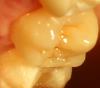

METT Опубликовано 22 марта, 2013 Автор Поделиться Опубликовано 22 марта, 2013 НОвенькое Ссылка на комментарий

METT Опубликовано 22 марта, 2013 Автор Поделиться Опубликовано 22 марта, 2013 И еще Ссылка на комментарий